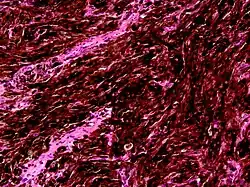

Histologically, the tumor is characterized by large, uniformly shaped polyhedral nevus cells that are pigmented and closely packed.[5] Typically, it lacks signs of malignancy, such as a high mitotic rate, necrosis, or infiltrative growth.[6] Similar to malignant melanoma, it exhibits an immunohistochemical profile with S-100 protein-, vimentin-, and HMB-45-positive tumor cells.[6]